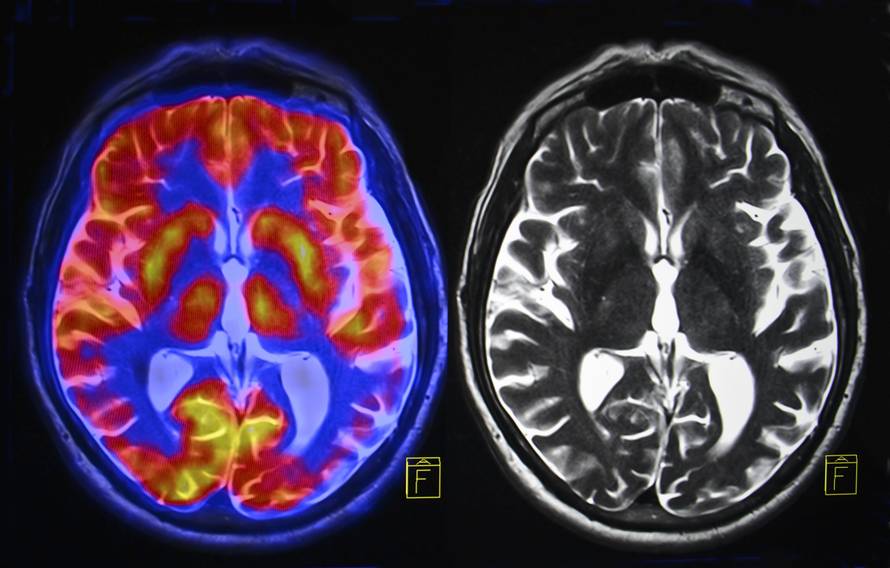

Istraživači bi pacijente tražili da zamišljaju određene stvari, kao što je igranje tenisa ili hodanje po vlastitoj kući kako bi im se aktivirali određeni dijelovi mozga.